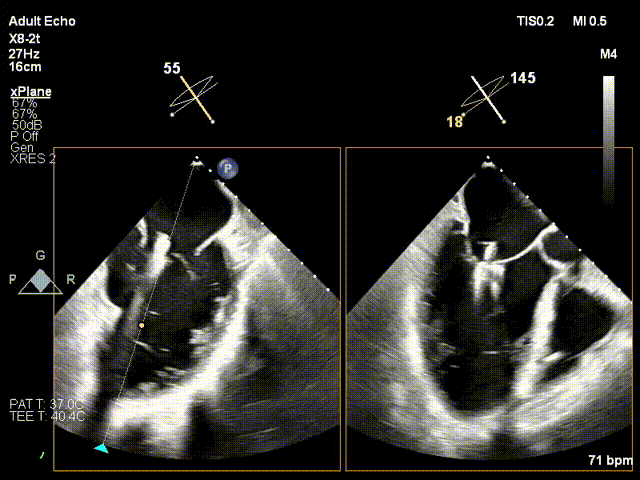

于2偏3区置入第一枚短宽夹

调整Orientation至11点50方向

进入瓣下,捕捞瓣叶

瓣叶捕获,Buncing明显

L侧有残余反流